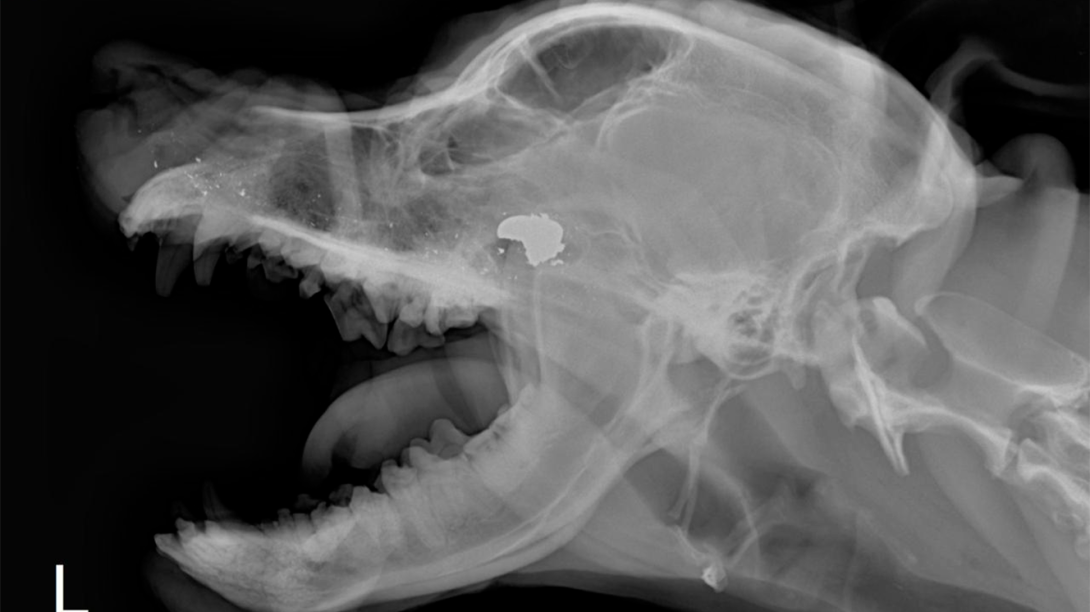

El incidente más reciente, que ha causado gran indignación involucra a una perra Pitbull que fue baleada. “El perro se encontraba a larga distancia de donde estaba la persona que le dispara. el hombre le dispara dos veces al perro. El perro en ningún momento lo atacó ni nada. Y simplemente el hombre saca su arma y le dispara con la excusa de que era que tenía miedo. No nos parece que eso sea bien hecho porque cuántos perros no le ladran en la calle y cuántos perros entonces piensa matar simplemente porque le ladra”, señaló el denunciante.

Afortunadamente, la perra logró sobrevivir gracias a la rápida intervención de algunas personas del sector que la llevaron rápidamente a un centro médico veterinario, donde fue sometida a una cirugía. “La perra actualmente se encuentra bien, pero la denuncia es de que esto no es el comportamiento que deberían tomar ellos. La verdad es que para eso está la ley, para eso están los policías, son una empresa que debería cuidar su prestigio”.